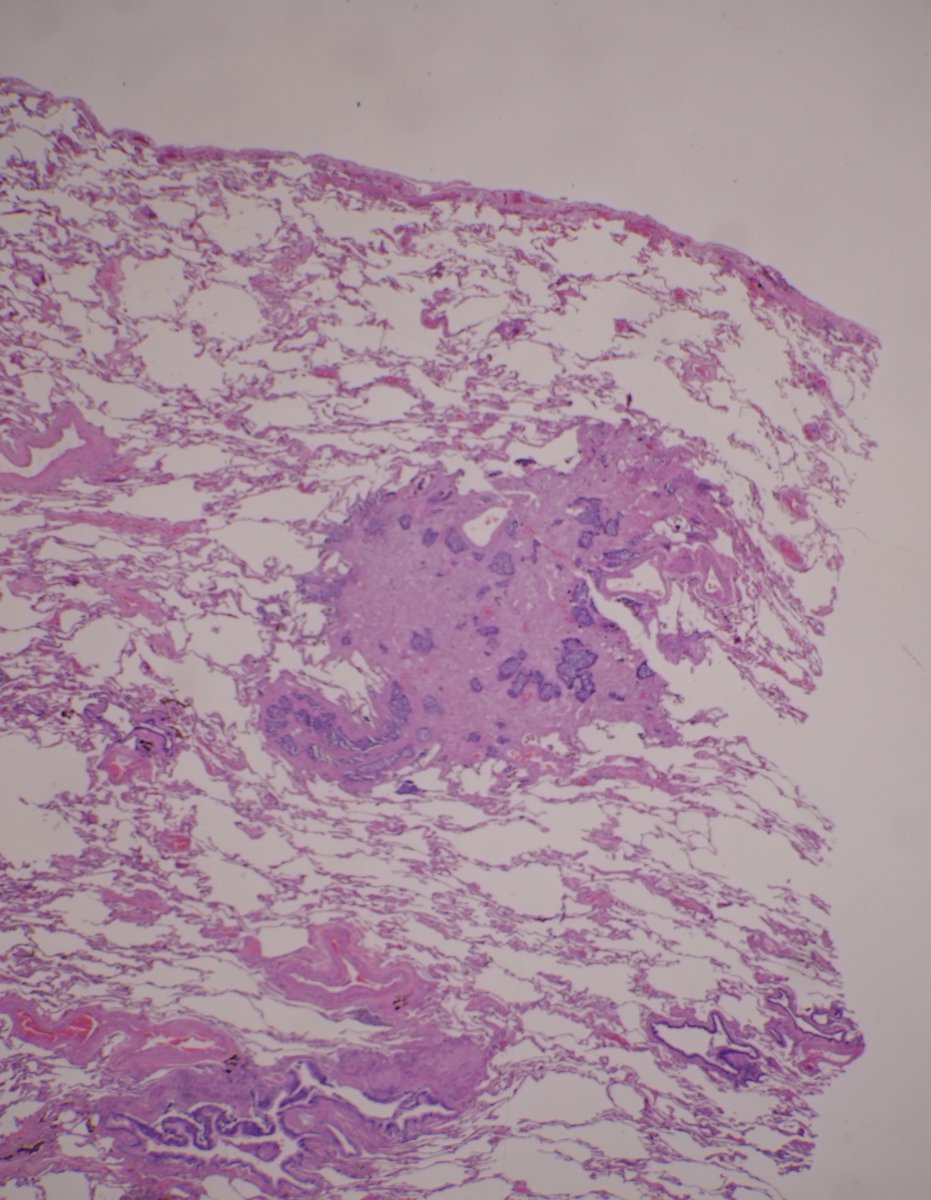

A: Lung Adenocarcinoma (in situ): Images showing emphysematous, lepidic growth pattern w/ increased presence of macrophages in the alveolar spaces, and a close-up of lepidic growing tumor cells around a blood vessel. @LungAssociation @UMRogelCancer #PulmonaryPath #DailyDX